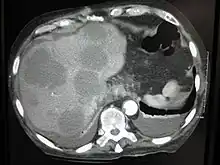

Pulmonary metastases shown on Chest X-Ray